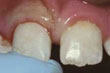

Chipped

Ukruszony ząb przedni